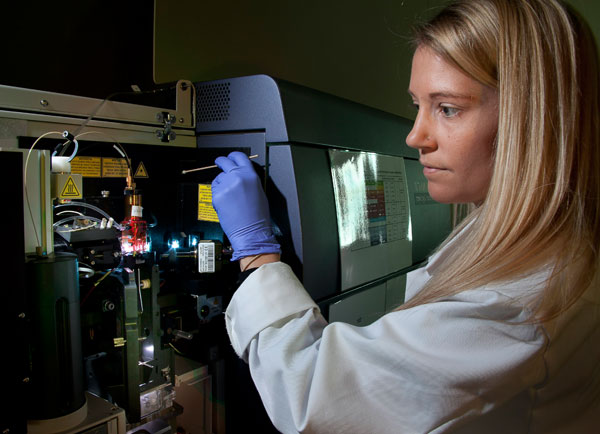

New technology uncovers complexities of colitis-associated colorectal cancer

Digital spatial profiling (DSP) tissue analysis is shedding new light on the molecular changes in colitis-associated colorectal cancer and signalling early biomarkers to identify t

Illuminating tumour micro environments

Advanced technical imaging capabilities and research projects supported by MWC are helping to identify new prognostic and diagnostic biomarkers to advance potential therapeutic tar

Smarter drug design

An advanced experimental technique linked to high powered computation is becoming an increasingly important tool for MWC researchers developing new drugs.